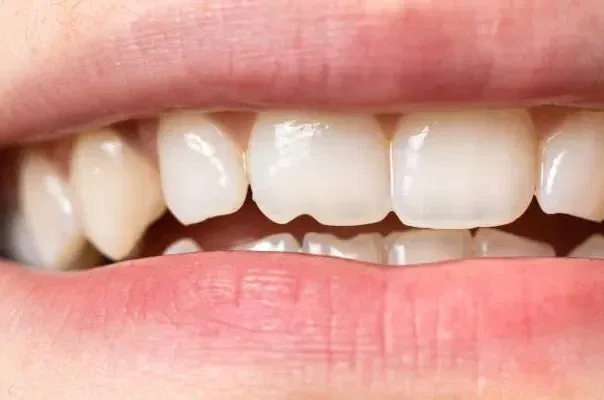

Before delving into the realm of natural remedies, it’s crucial to understand the nature of a cracked tooth and what can and cannot be achieved through natural means. A cracked tooth typically occurs due to a variety of factors, including trauma, teeth grinding (bruxism), and even biting into hard foods. The extent of the crack can range from superficial lines on the enamel to more severe fractures that extend deep into the tooth’s structure.

While natural remedies can help manage the symptoms and promote oral health, they cannot magically mend a severely cracked tooth or replace the need for professional dental care. Cracked teeth require appropriate dental intervention, such as bonding, crowns, or root canals, depending on the severity of the damage.